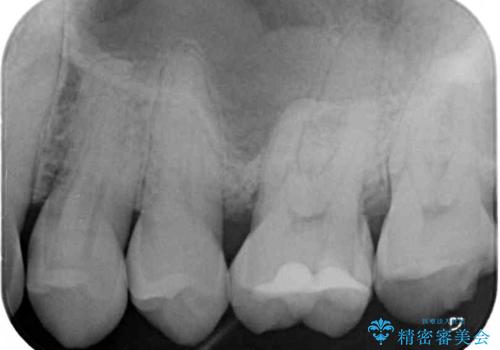

- 食事で堅いものを噛んだ時に歯が欠けてしまったとのことで来院された患者様です。

咬合面に大きな修復物が入っており、その境目から破折し、歯肉の内側の歯根にまで破折が及んでいました。

残念ながら神経組織が露出しており、根管治療が必要となっていたため、まずは根管治療を行うこととしました。